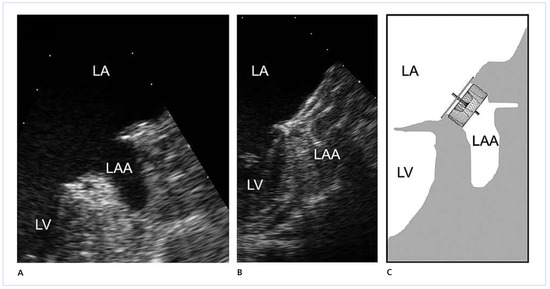

Transcatheter Left Atrial Appendage Closure in Patients with Atrial Fibrillation

by Michael Schmid, Steffen Gloekler, Ardan M. Saguner, Andreas Wahl, Urs Fischer, Marcel Arnold, Ahmed A. Khattab, Fabian Nietlispach, Enio Guerios, Peter M. Wenaweser, Stephan Windecker and Bernhard Meier

Cardiovasc. Med. 2013, 16(4), 123; https://doi.org/10.4414/cvm.2013.00145 - 17 Apr 2013

Background: Atrial fibrillation (AF) carries an increased risk of systemic thrombo-embolism. More than 90% of emboli in non-valvular AF originate from the left atrial appendage (LAA). Percutaneous closure of the LAA offers an alternative to long-term oral anticoagulation (OAC). Amplatzer devices have [...] Read more.

Background: Atrial fibrillation (AF) carries an increased risk of systemic thrombo-embolism. More than 90% of emboli in non-valvular AF originate from the left atrial appendage (LAA). Percutaneous closure of the LAA offers an alternative to long-term oral anticoagulation (OAC). Amplatzer devices have been proposed for this. A dedicated device (Amplatzer Cardiac Plug [ACP]) has been introduced to improve safety and efficacy compared to non-dedicated devices (NDAs, atrial and ventricular septal occluders) used previously for LAA closure. Objective: The present study investigated procedural and clinical outcomes of LAA closure with the new ACP compared to NDAs. Methods: All patients with LAA closure using an Amplatzer device at the Bern University Hospital, were entered into a prospective registry. Trans-oesophageal echocardiography (TEE) preceded LAA closure which was performed under local anaesthesia and fluoroscopic guidance only. Correct device position was documented by fluoroscopy and before discharge by trans-thoracic echocardiography (TTE). Follow-up TEE and clinical assessment by a neurologist were performed 3–9 months later. A later follow-up was performed by telephone contact. Results: A total of 64 consecutive patients (NDA group n = 32, June 2002 to December 2008; ACP group n = 32, January 2009 to March 2010) were included. The thromboembolic CHADS2 score risk was lower in the NDA group compared to the ACP group (1.0 ± 1.0 versus 2.5 ± 1.3, p = 0.44). Despite a lower rate of combined interventions, total fluoroscopy time and total amount of contrast medium were higher in the NDA group (28 ± 13 min versus 19 ± 20 min, p = 0.06, and 424 ± 182 ml versus 226 ± 134 ml, p <0.01, respectively). In the NDA group, the techni - cal success rate was 84%, compared to 100% in the ACP group (p = 0.02). Device embolisation occurred in 5 (16%) patients in the NDA group but did not occur in the ACP group (p = 0.02). The incidence or suspicion of thrombus on devices were: 2/17 (12%) in the NDA and 6/28 (21%) in the ACP group (p = 0.10). During followup (mean 7.2 ± 2.7 months, NDA long-term follow-up 75 ± 16 months), no cerebrovascular accidents (CVA) occurred in either group. Conclusion: The ACP facilitated the transcatheter LAA closure procedure and improved its safety compared to NDAs. It promises to enhance their favourable long-term results. Full article

Figure 1